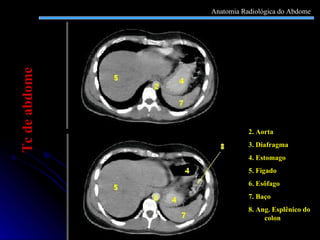

2. Aorta 3. Diafragma 4. Estomago 5. Fígado 6. Esôfago 7. Baço 8. Ang. Esplênico do colon Tc de abdome Anatomia Radiológica do Abdome

2. Aorta 3.Diafragma 4. Estomago 5. Fígado 6. Esôfago 7. Baço 8. Ang. Esplênico do colon Tc de abdome Anatomia Radiológica do Abdome